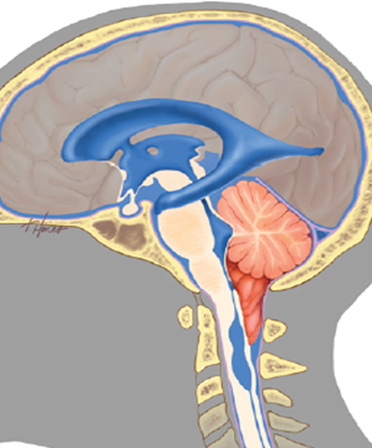

키아리 기형의 치료는 기형의 정도 및 증상의 심각성과 특성에 따라 다릅니다. 증상이 없으면 정기적인 검사와 MRI로 모니터링하며 다른 치료를 권장하지 않습니다. 가벼운 두통이 주요 증상인 경우 진통제 등의 약물 치료를 할 수 있습니다. 일반적으로 증상이 있는 키아리 기형은 수술 (후두와 감압술)로 치료합니다. 이는 가장 일반적인 수술 방법으로 두개골 뒤쪽 하부에 있는 뼈의 작은 일부분을 제거하여 공간을 만들어 소뇌와 척수에 가해지는 압력을 완화하여 뇌와 척추강의 해부학적 변화의 진행을 막고 증상을 완화하거나 안정화시키게 됩니다.

후두 감압술

파란색 부위의 두개골 일부와 경추 후궁을 제거해 후두와의 소뇌에 대한 압력을 줄여줍니다.